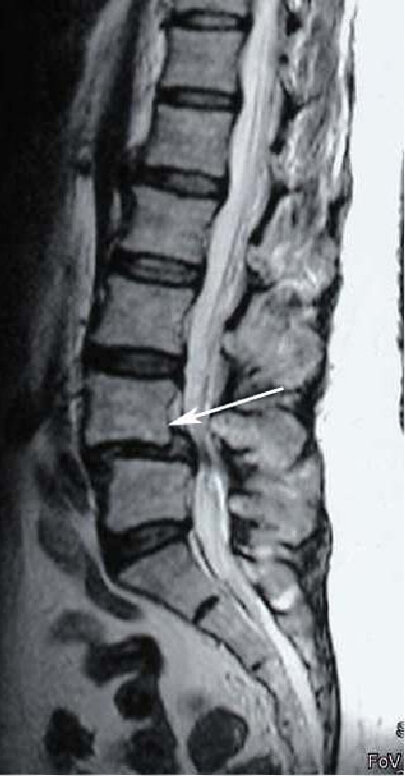

Смещение L4 позвонка вперёд

Дегенеративный листез L4 позвонка